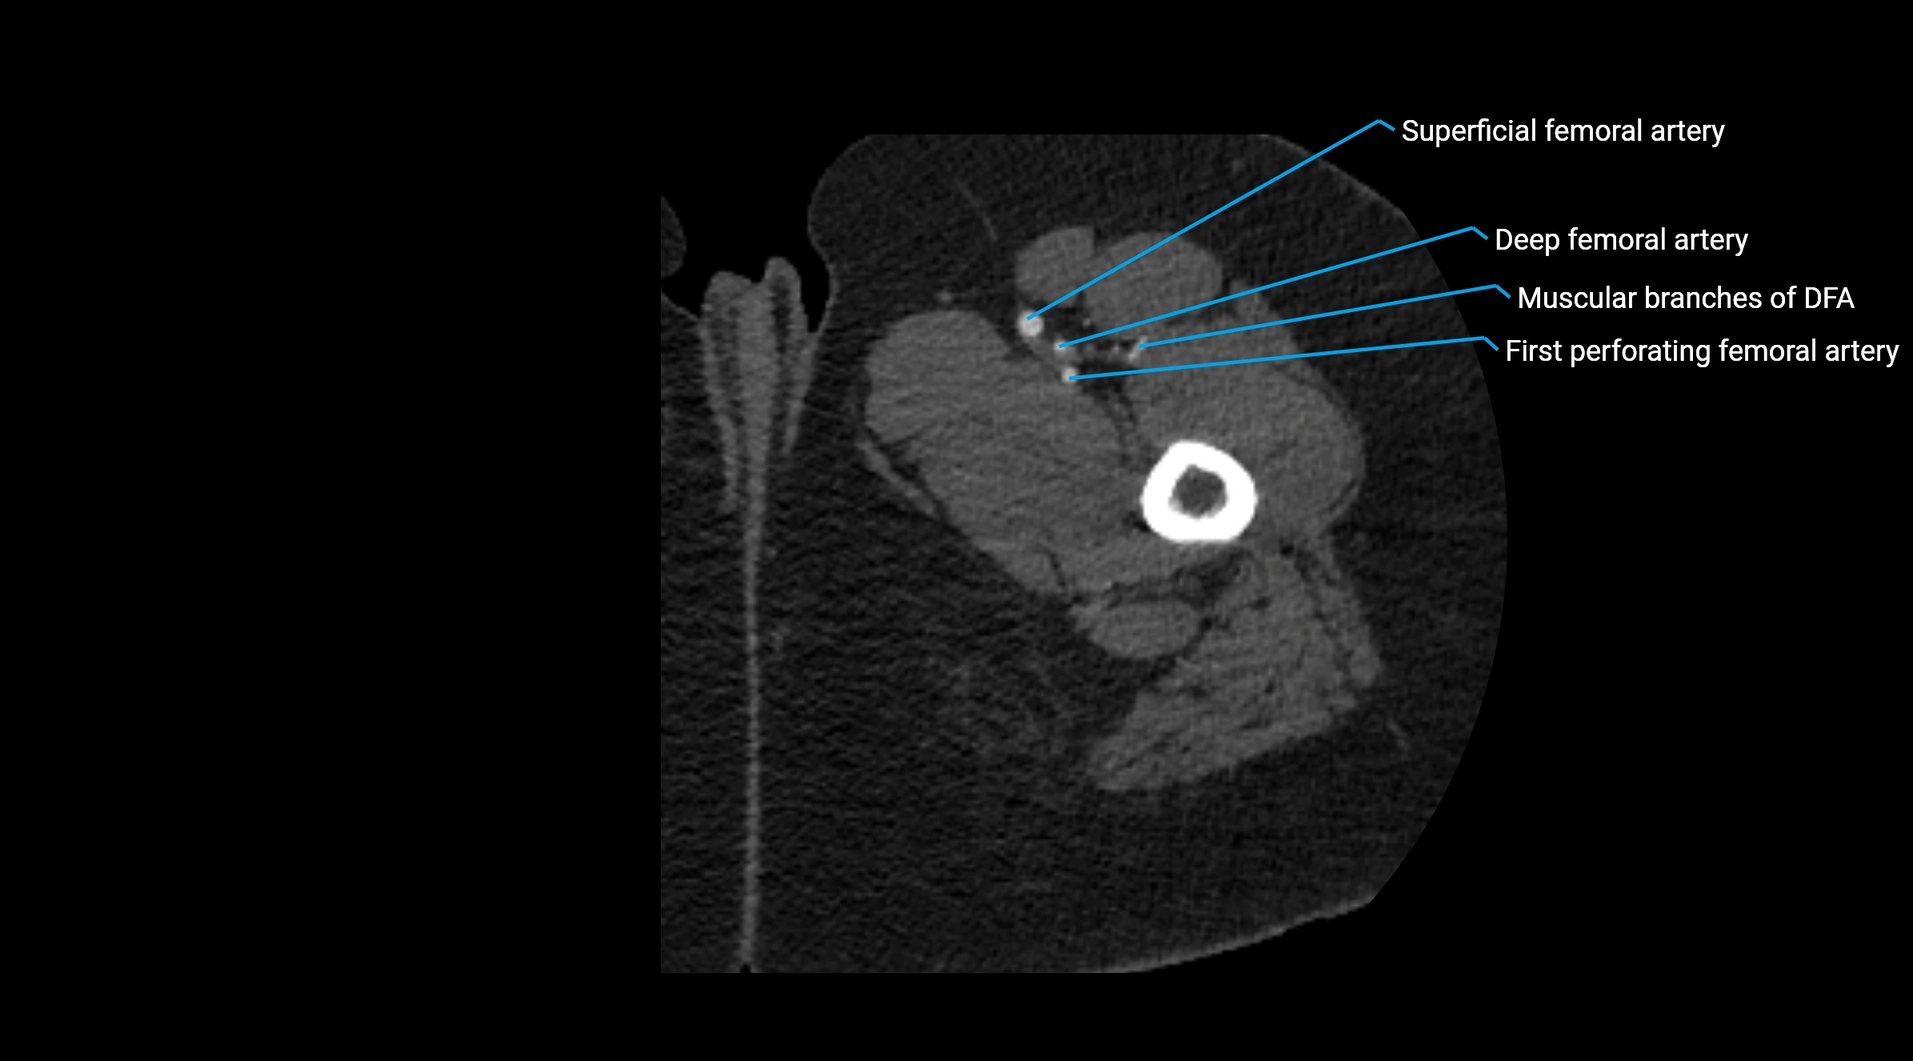

CT images

image